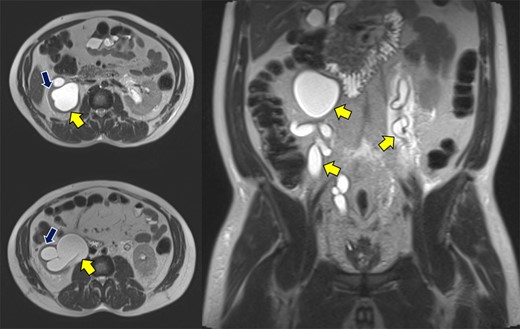

Abdominopelvic MRI T2-weighted imaging demonstrated severe bilateral hydroureteronephrosis (Fig. 1, yellow arrows) with thinning of the right renal cortex (blue arrow), suggestive of chronic obstruction.

Abdominopelvic MRI T2WI demonstrating severe bilateral hydroureteronephrosis (yellow arrows) with thinning of the right renal cortex (blue arrow).